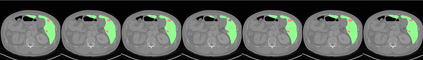

UNet and its variants have been widely used in medical image segmentation. However, these models, especially those based on Transformer architectures, pose challenges due to their large number of parameters and computational loads, making them unsuitable for mobile health applications. Recently, State Space Models (SSMs), exemplified by Mamba, have emerged as competitive alternatives to CNN and Transformer architectures. Building upon this, we employ Mamba as a lightweight substitute for CNN and Transformer within UNet, aiming at tackling challenges stemming from computational resource limitations in real medical settings. To this end, we introduce the Lightweight Mamba UNet (LightM-UNet) that integrates Mamba and UNet in a lightweight framework. Specifically, LightM-UNet leverages the Residual Vision Mamba Layer in a pure Mamba fashion to extract deep semantic features and model long-range spatial dependencies, with linear computational complexity. Extensive experiments conducted on two real-world 2D/3D datasets demonstrate that LightM-UNet surpasses existing state-of-the-art literature. Notably, when compared to the renowned nnU-Net, LightM-UNet achieves superior segmentation performance while drastically reducing parameter and computation costs by 116x and 21x, respectively. This highlights the potential of Mamba in facilitating model lightweighting. Our code implementation is publicly available at https://github.com/MrBlankness/LightM-UNet.